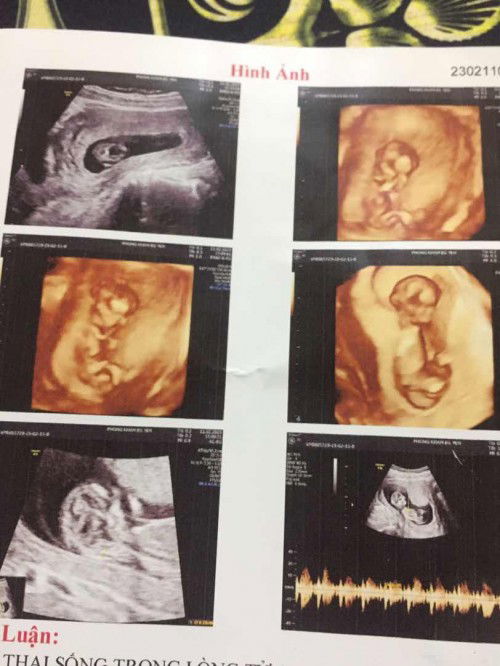

em bé đang nằm nghiêng, bạn đi khám tư ấy rồi hỏi bác sĩ là trai hay gái thì bác sĩ sẽ chỉ cho bạn nha.

Nhỏ quá k nhìn rõ mom ơi. Bsi chuyên môn mới nhìn đc thôi

bs nhìn chuẩn hơn, ảnh này khó nhìn quá mom au

cái này phải bác sĩ mới nhìn ra nè m

Bác sĩ siêu âm nhìn mới chuẩn mom à

mh k rõ, sao mom k hỏi bác sĩ luôn

nhìn k rõ luôn